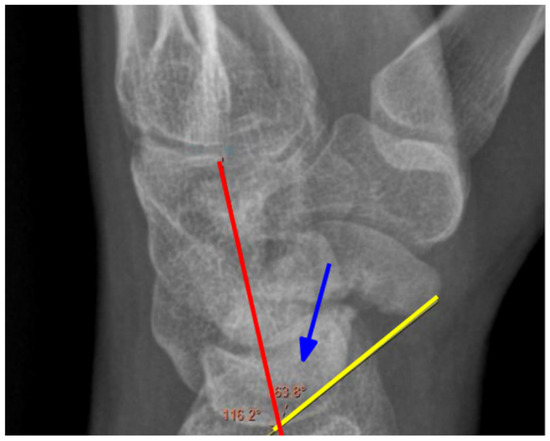

2.2. Radiological Assessment